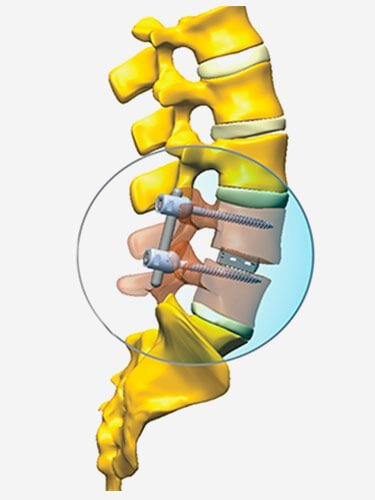

Trata-se de um procedimento cirúrgico realizado a partir da união de ossos selecionados na coluna, a fim de sanar problemas como dores e aprimorar a estabilidade do paciente.

A artrodese pode ser acompanhada ou não de “cages” (do francês e inglês: quer dizer “gaiola”). Os cages são estruturas que ocupam o espaço deixado pela remoção do disco intervertebral conferindo aumento de estabilidade à coluna e ao sistema de artrodese.

Artrodese lombar por via posterior: Acesso por trás com utilização de implantes metálicos para fixação das articulações e colocação de enxerto ósseo para a fusão entre as vértebras.

A artrodese pode necessitar de instrumentos, ou seja, alguns materiais especiais, como, por exemplo, pinos, placas, parafusos, barras e cages, estes últimos são dispositivos intersomáticos que substituem o disco. No entanto, o que causa a fusão óssea é a colocação de enxerto, o qual pode ser conseguido pelo próprio pacientes ou ainda através de industrialização. Graças à tecnologia atual, os equipamentos possibilitam a realização deste procedimento da coluna de maneira minimamente invasiva, por meio de pequenos incisões na pele e com a mínima agressão aos tecidos adjacentes.